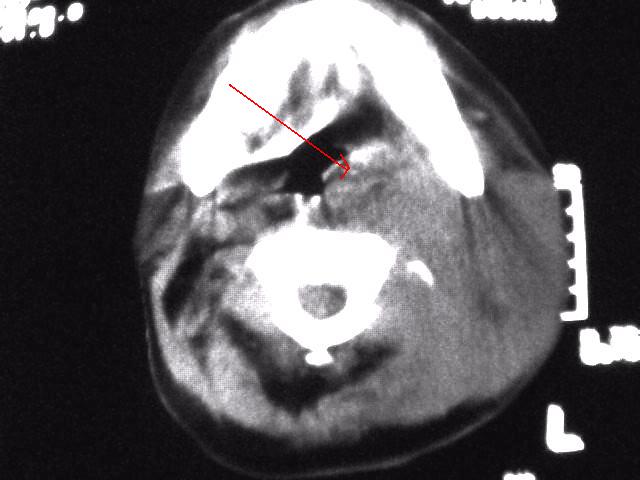

颈部层厚10mm间距10mm连续扫描及增强扫描共24层示:左侧下颈部胸锁乳突肌内侧区域内可见多发软组织结节,密度不均,内可见斑片状低密度区,大小不等,部分融合成块,左侧融合成一块者大约9.0x5.4,与周围肌肉、血管等结构界面不清,骨质未见明显浸润影。左侧锁骨下可见多个软组织结节,与周围界限尚清,左侧锁骨上窝内可见一大软组织肿物,大小约4.7x3.7cm,内密度欠均匀中心可见低密度区。

考虑:左侧颈部及双侧锁骨下多发淋巴结肿。非何杰金氏淋巴瘤可能性大,建议进一步检查。

1)考虑为:淋巴瘤或转移瘤。建议:活检。2)左侧眼球痨。